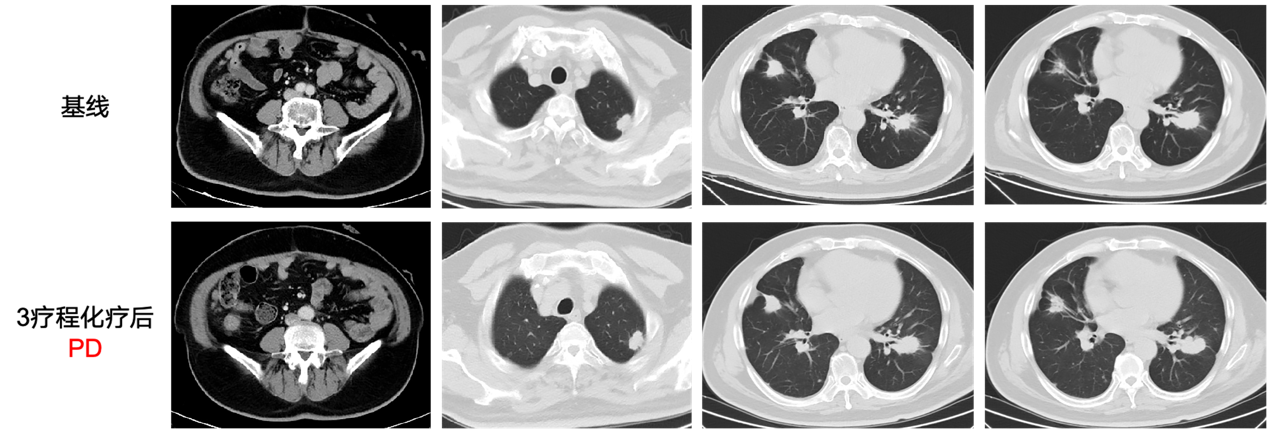

二线治疗

2024.11-2025.01

行FOLFIRI+贝伐珠单抗方案3个周期后PD,治疗期间出现 1级中性粒细胞减少不良反应,对症治疗后好转,PFS2为2个月。

图片2png.png

图3 影像学评估